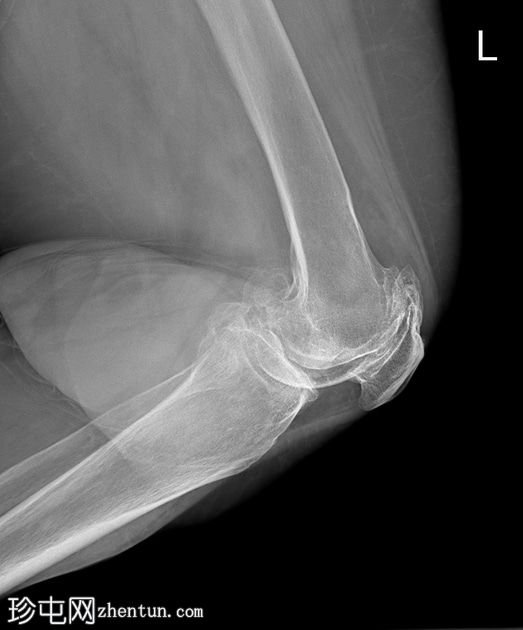

双膝X线片

X线片

正位片

侧位片

双侧胫股关节间隙明显变窄,伴软骨下硬化。

双侧髌股关节间隙变窄。双侧股骨和胫骨关节周围骨赘及髌骨骨赘。

右侧股骨远端软组织内可见多发致密钙化分叶状病变。未见骨折、骨膜反应或骨损伤。无内翻或外翻畸形。

本病例展示了继发性滑膜软骨瘤病伴严重膝骨关节炎的典型

影像

学表现。